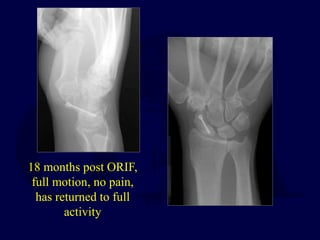

18 months post ORIF,

full motion, no pain,

has returned to full

activity

18 months postORIF, full motion, no pain, has returned to full activity